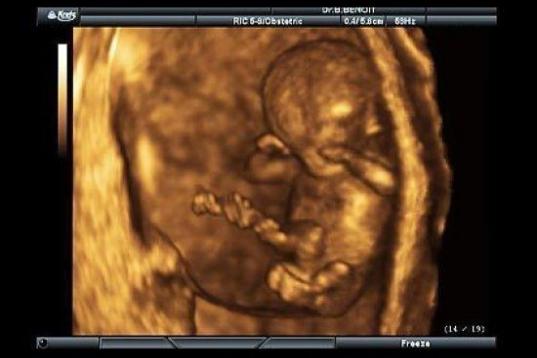

En esta galería puedes ver en fotos como es el desarrollo de un feto de semana en semana:

Desarrollo del feto, en fotos